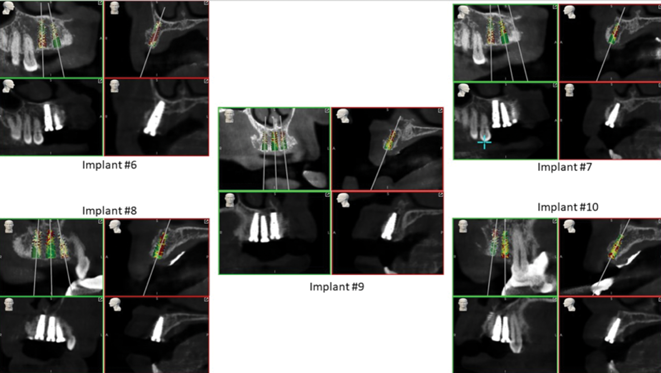

The all-digital treatment plan was prosthetically driven (Figure 2), with the clinician mindful of the critical urgency for optimal implant placement, with implants ideally 3 mm apart with most of the interproximal osseous crest maintained9 and with strict adherence to the design of the plan, based on Tarnow et al's esthetic guidelines for the maxillary anterior esthetic zone.10 The clinical team elected to use robotic guidance (Yomi® Dental Robotic System, Neocis, neocis.com), which on the day of surgery permits fiducial markers to verify the accuracy of placement, angulation, and depth.

In preparation for the surgical procedure, modest bone grafting and soft-tissue augmentation was used to create more ideal oral parameters to receive the implants. Five implants (NobelActive®, Nobel Biocare, nobelbiocare.com) were placed in the maxillary anterior esthetic zone using haptic robotic guidance (Figure 3 and Figure 4). The procedure was entirely flapless, contributing to minimizing trauma for the patient. The surgeon, in full control of the robot, guided the arm to the planned implant positions while inspecting the soft-tissue type at the emergence, noting the bone quality, and monitoring adherence to the plan with the robotic system's intraoperative accuracy verification. The real-time audio and visual updates confirmed that the clinical parameters had been successfully achieved.

Postoperative CBCTs indicated a high level of accuracy adhering to the planned implant placement, with minimal compromise to the surrounding soft tissue (Figure 5). For the restorative dentist, the delivery of this highly accurate implant placement in ideal quality bone helped ensure that a robust foundation was securely in place for the definitive prostheses. During the healing period of 4 months, the patient wore a removable provisional prosthesis.

Fig 5. Postoperative CBCT analysis showing accurate placement of the five anterior implants.

Figure 5